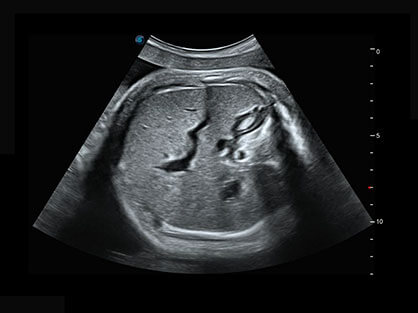

临床图